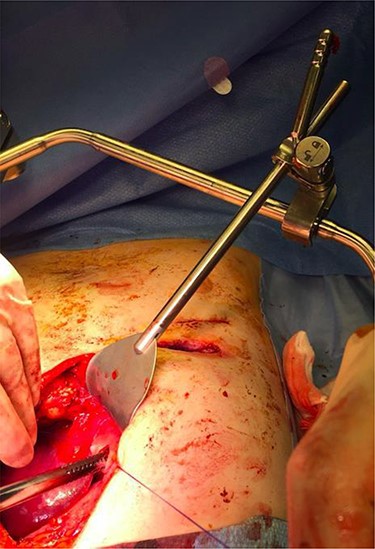

Superior lateral intraoperative view of the laparotomy used to access and remove the second migrated bar.

Superior intraoperative view of the laparotomy used to access and remove the second migrated bar.

Our patient was followed up annually. After two and half years, he developed a right-sided wound infection, initially treated with antibiotics. It was decided to remove the bar for prevention of recurrent infection. The chest X-ray showed migration of the lower-placed bar (Fig. 2). The upper bar and associated stabilizers were removed through the bilateral small incisions without any complication; however, the lower bar was not palpable. Therefore, a left-side thoracotomy was performed; however, the bar was not found in the chest. The incision was extended to a midline laparotomy (Fig. 3). This revealed an erosion of the bar in to the stomach after passing over the left lobe of the liver (Fig. 4). The bar and stabilizers were completely removed, and the hole in the stomach was closed directly with sutures. The patient was discharged home without any further complication after successful recovery.